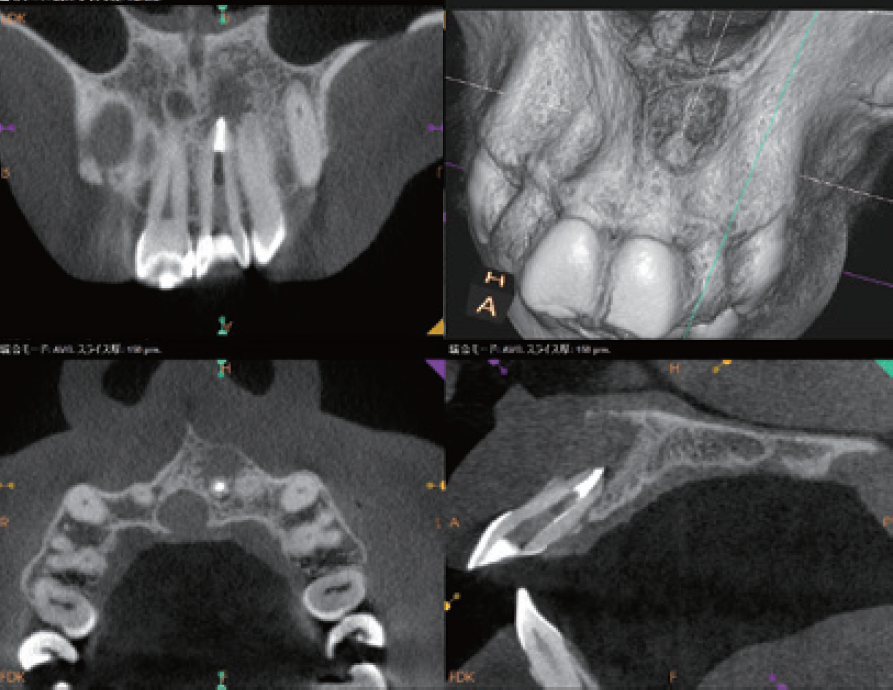

「臨床症例3」2022年9月16日に上顎前歯部腫脹と鈍痛を主訴に紹介元の歯科医院を受診

●年齢 40代 男性

難治性歯内療法疾患と診断を受け、当院を紹介される。同年10月19日当院を受診。問診時、10代の時に前歯部を強打し歯科医院を受診するも経過観察のまま放置していたとのことで、上顎左側中切歯の根尖部が外部吸収様の形態が確認でき、根尖孔もかなり開いていることが予測できた。CBCTでは唇側皮質骨は開窓し、根尖病変は中切歯、側切歯の根尖部を含む広範囲に広がっていることが確認できる。治療においては根尖孔のゲージングで#100とし、作業長の1ミリアンダーに止まるリーマー#120で抵抗形態を付与し、MTA製剤の根尖外への溢出を極力抑えるように努めて根尖部の閉鎖を行った。

その次に、上顎左側側切歯の感染根管処置を行った。側切歯は中切歯とは違い、狭窄が進行し穿通障害歯を呈していた。穿通し作業長を確認し、根管充填を行った。術後3ヶ月、1年の状態は治癒傾向が継続しており、臨床症状も無い。外科的アプローチを回避できる結果となった。

臨床症例3 その1

①初診時(2022/10/19)

左上1、2番の根尖部を含む大きさの根尖病変が認められる

左上1は根尖部は外部吸収が認められる

②左上1番 EMR時レントゲン像

根根尖孔径は#100に相当した

③MTA製剤を用いて根管充填を行なった

作業長1ミリアンダーに#120のリーマーにて抵抗形態を付与しMTA製剤が根尖外に多量に溢出しないように努めた

④根管口まではガッタパーチャとMTAシーラーを用いて充填した

臨床症例3 その4

左上1番の根尖部にMTA製剤充填時のCBCT像

唇側皮質骨は大きく開窓し、根尖病変の大きさが鼻腔底付近まで広がっていることが確認できる

臨床症例3 その5

術後1年のCBCT像

根尖周囲に見られた根尖病変はほぼ消失し、唇側皮質骨の開窓も改善したことが認められる